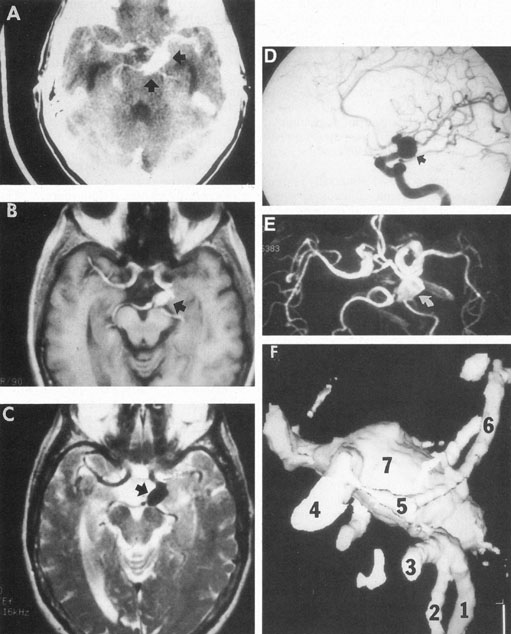

Aneurysms that primarily arise form the carotid system at the origin of the posterior communicating artery are of special interest to neurologists, neurosurgeons, and ophthalmologists because they tend to involve the oculomotor nerve. The classic presentation is sudden onset of severe unilateral frontal headache, ptosis, limitation adduction, depression and elevation of the eye, and dilated and fixed pupil. The cerebrospinal fluid is grossly bloody, and angiography is diagnostic (Fig. 5). Pain in and around the eye in the trigeminal–ophthalmic distribution is a conspicuous symptom, but sensory defects are absent. Clinical and pathologic evidence indicates that impairment of function by a contiguous aneurysm usually occurs in conjunction with hemorrhage into the oculomotor nerve that, along with sudden distortion, can produce referred pain.27

Fig. 5. Aneurysm at the junction of the internal carotid and posterior communicating arteries. A: Contrast-enhanced axial computed tomography (CT) shows a large aneurysm (arrows). Magnetic resonance imaging (MRI) studies effectively demonstrate the aneurysm. B: T1-weighted MRI with gadolinium. C: T2-weighted (arrow indicates black flow void). D: Selective internal carotid angiogram. E: Magnetic resonance angiogram (MRA; curved arrow) shows the same aneurysm. F: Helical image-intensified CT technique provides quasi-three–dimensional mold of arteries: 1. right posterior cerebral; 2. posterior superior cerebellar; 3. basilar; 4. internal carotid; 5. posterior communicating; 6. left posterior cerebral; 7. supraclinoid aneurysm, same as depicted in A through E. (Courtesy of Dr. Raphael Aponte.)